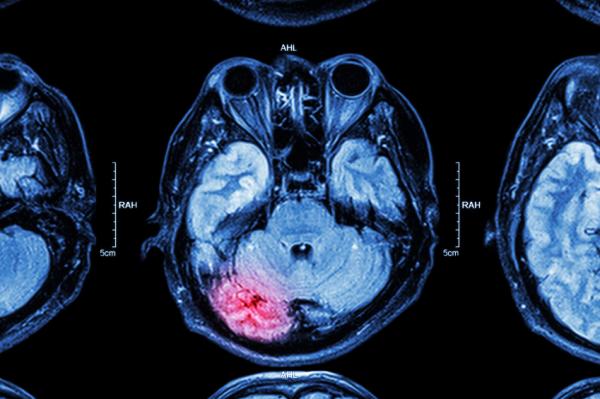

• Accidente cerebro vascular o ACV

Si la arteriosclerosis se presenta en las arterias carótidas, encargadas de llevar sangre con oxígeno al cerebro, se pueden presentar los siguientes síntomas:

• Dolor de cabeza intenso que surge de forma repentina

• Parálisis corporal

• Adormecimiento de una zona del cuerpo como el rostro, los brazos o las piernas que generalmente se presenta de un lado del cuerpo

• Problemas para hablar o para comprender lo que otro dice

• Problemas de visión por uno o ambos ojos

• Debilidad

• Problemas de coordinación motora

• Pérdida del conocimiento

Estos síntomas pueden indicar un bloqueo importante de la arteria carótida e incluso la presencia de un ACV, por lo que acudir de inmediato al un médico es fundamental.